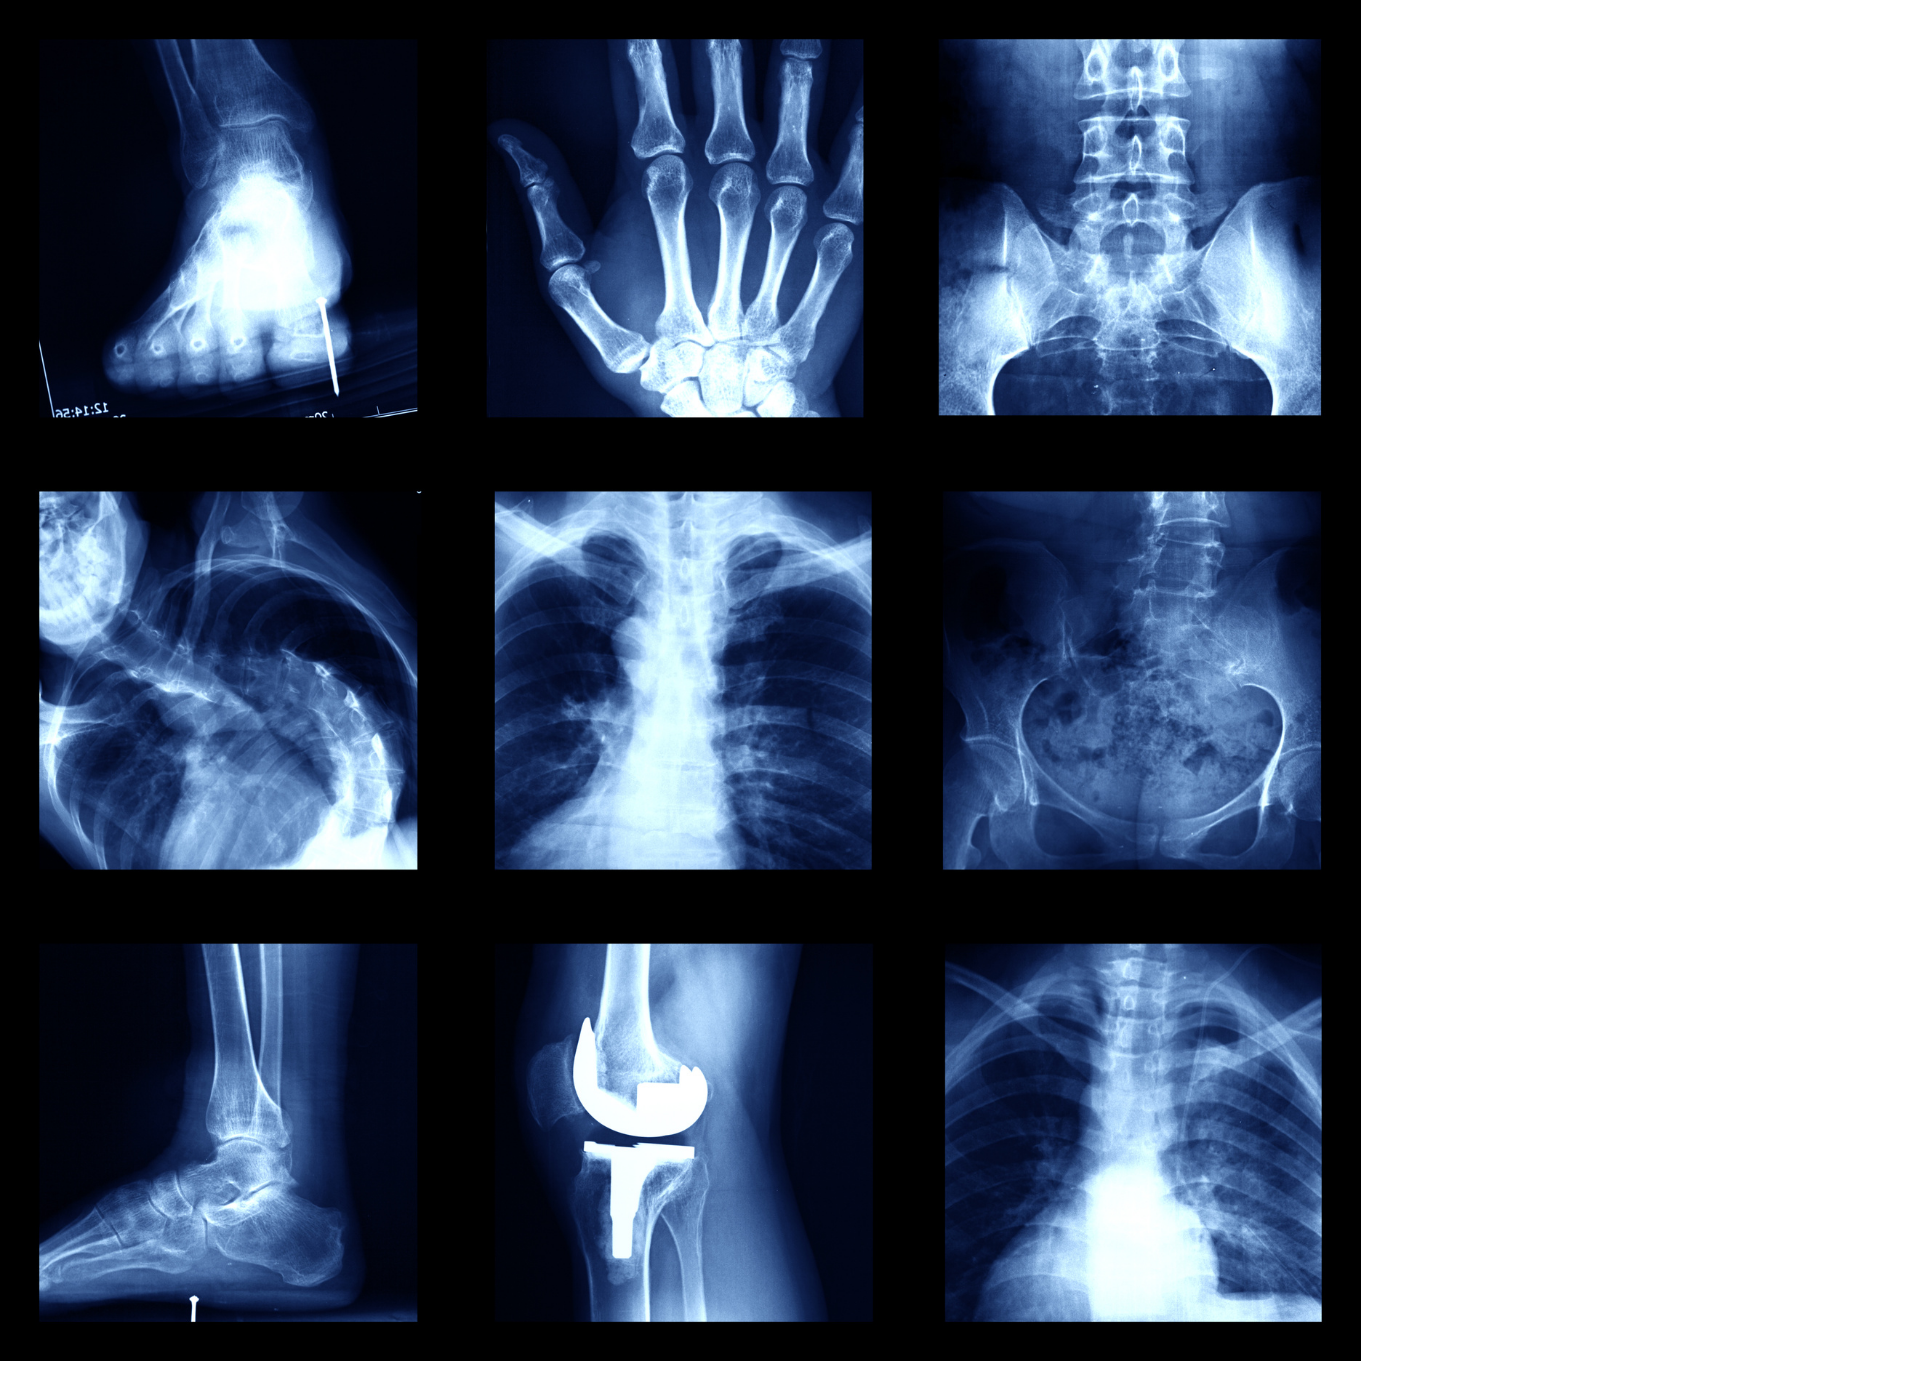

Это было 125 лет назад. Ученого звали Вильгельм Рентген, а открытое им явление сегодня известно всему миру как рентгеновское излучение. В наши дни врачи-рентгенологи по всему миру проводят свыше 40 млн рентгенологических процедур в год.

Со времен Рентгена наука серьезно продвинулась вперед: созданы и усовершенствованы новые возможности диагностики и лечения самых разных, в том числе тяжелых заболеваний.